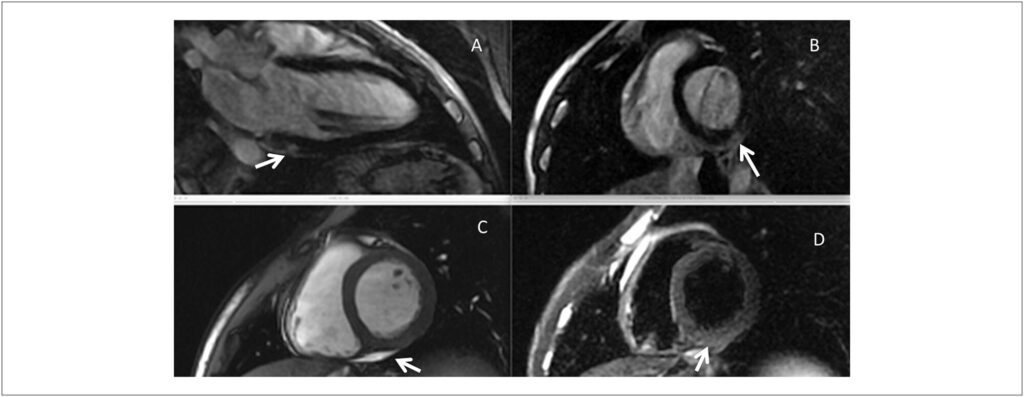

O padrão típico da injúria miocárdica e da fibrose subsequente em pacientes com miocardite viral é subepicárdico. Entretanto, outros padrões de injúria e lesões, conforme detectados pelos estudos utilizando ressonância magnética cardíaca, também ocorrem comumente, incluindo a injúria subendocárdica, que reproduz o padrão da doença cardíaca isquêmica, e lesão circunferencial no meio da parede, vista com mais frequência em pacientes com doença avançada e cardiomiopatias dilatadas. Nos pacientes com miocardite que apresentam arritmias malignas no cenário de função do ventrículo esquerdo (VE) preservada, não é raro encontrar o padrão de lesão subepicárdica na presença de função sistólica do VE normal ou levemente anormal. No entanto, a patogênese da lesão subepicárdica em pacientes com miocardite acompanhada ou não por disfunção significativa do VE ainda não está clara.

Além da miocardite, a lesão miocárdica subepicárdica é encontrada em associação com vários processos de doenças que não são considerados resultantes de injúria miocárdica induzida por vírus. A lista inclui processos de doenças com etiologias díspares, tais como as doenças de Duchenne e de Fabry, a cardiomiopatia chagásica e a doença cardíaca reumática, entre outras.– Portanto, teorias diferentes já foram propostas para explicar esse padrão de formação de lesão em pacientes com patologias diferentes. O aumento de tensão localizada excessiva e alterações de perfusão locais já foram postulados como mecanismos que contribuem para isso, mas não são suficientes para serem considerados mecanismos principais. A tensão da parede calculada é mais alta no nível subendocárdico, e defeitos de perfusão resultantes de isquemia geralmente são subendocárdicos. Após a formação da lesão, a perfusão é diminuída em proporção à redução de densidade capilar (defeito corrigido), mas isso não implica que a isquemia local seja o mecanismo patogenético subjacente à formação de lesão subepicárdica.